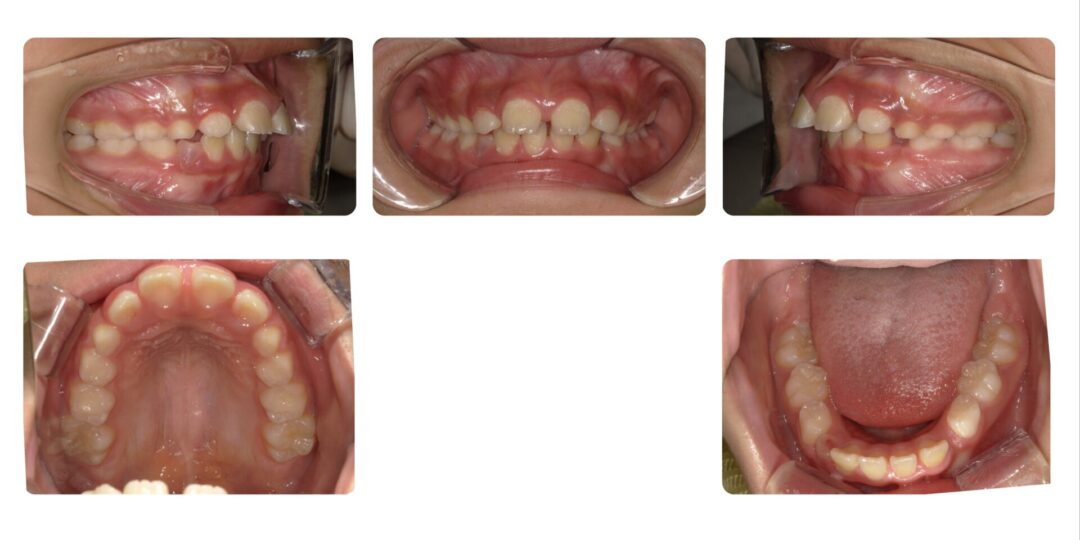

矯正治療後

治療内容

第一期治療 拡大ねじ付きバイオネーター

治療期間

1年9か月

治療費用

自由診療 基本料金¥330,000 処置料¥3,300